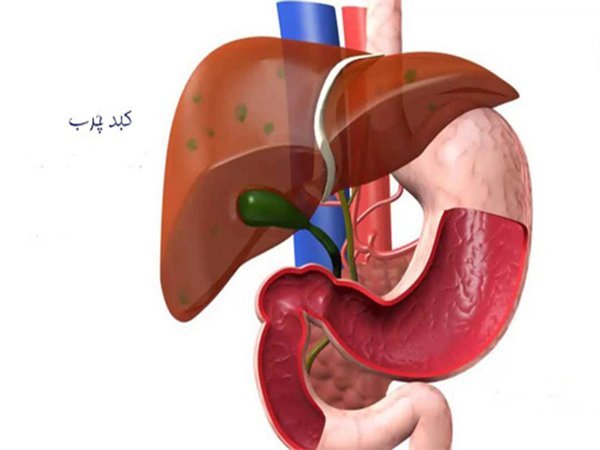

کبد چرب

کبد چرب

کبد چرب (Fatty liver) یا استئاتوز واژه کلی برای اشاره به جمع شدن چربی در کبد است. وجود چربی در کبد، طبیعی میباشد، اما اگر این میزان از چربی بیشتر از ۵ تا ۱۰ درصد وزن کل کبد شود، فرد به بیماری کبد چرب دچار شده است. کبد چرب یک بیماری درمان پذیر است ولی بعضی اوقات میتواند باعث اثرات و عوراض خطرناکی شود. کبد چرب معمولا نشانه و علامتی نداشته و باعث آسیبی همیشگی و برگشت پذیر نمیشود.وظیفه کبد بررسی هر غذایی که میخوریم و هر نوشیدنی که مینوشیم برای تصفیه مواد خطرناک است. اگر میزان زیادی چربی در کبد وجود داشته باشد، این فرآیند دچار مشکل میشود. در بعضی از مواقع کبد چرب باعث التهاب و یا زخم های کبدی میشود. در شدیدترین حالت کبد چرب فرد دچار نارسایی کبدی میشود. اکثر موارد کبد چرب در سنین بین ۵۰ تا ۶۰ سال تشخیص داده میشود. زمانیکه کبد چرب بدلیل سایر مشکلات رخ میدهد، خطرناک بوده و باید به موقع برای درمان اقدام کرد.